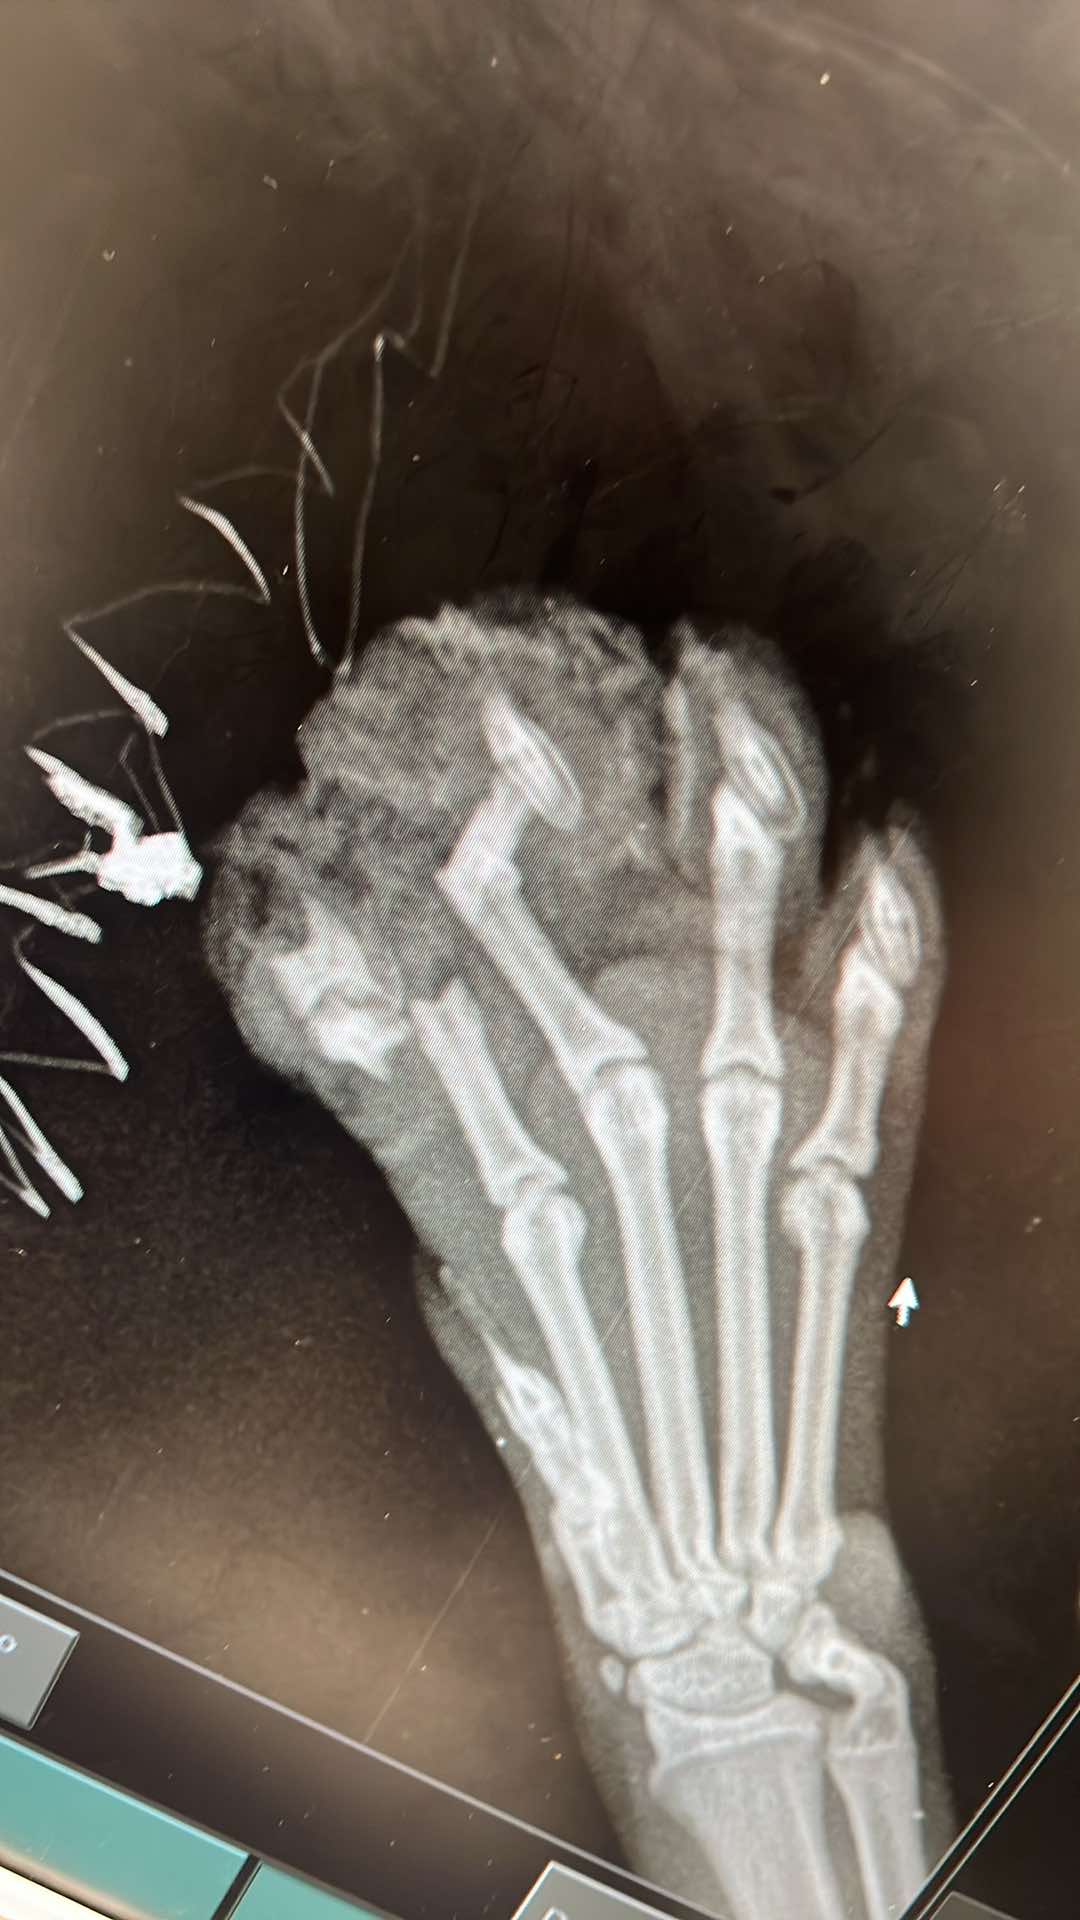

Jego łapka była prawdopodobnie zmiażdżona, a kosteczki paluszków połamane (widać na zdjęciach rtg). Dodatkowo miał złamanie (wyrwanie) kości łokciowej.

W pierwszej kolejności kotek został zoperowany w Davet Radłów przez dr Mączkę. Łapka została pozszywana, kotek miał naświetlania i żelowe opatrunki, tak aby przyspieszyć gojenie. Następnie Zeus przeszedł operację łokcia w ArWet w Wieliczce. Kotek został też wykastrowany.